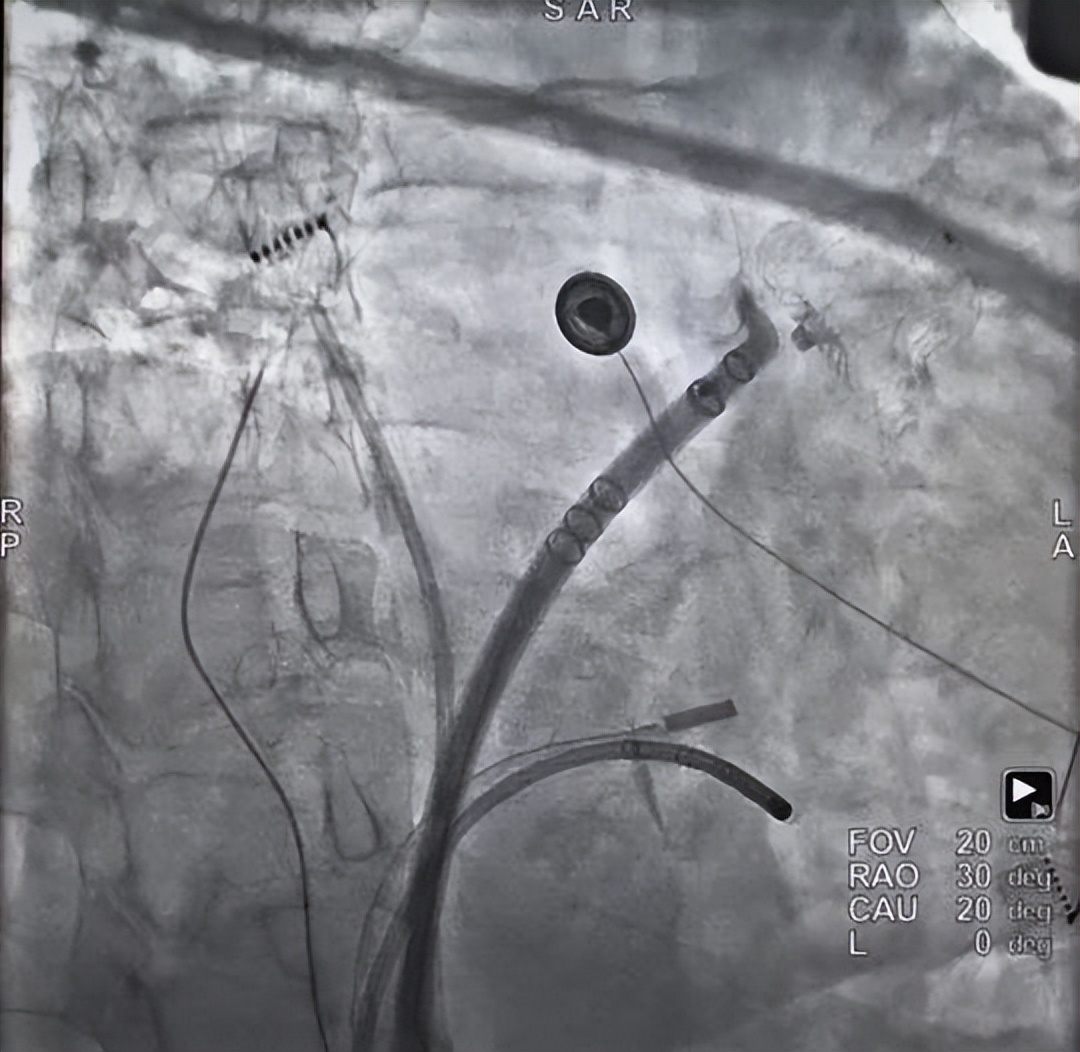

手术过程中,王洪涛副主任带领范博渊主治医师、孙阳住院医师以及毛宝、王艺鹏、吴娇等进修医师,在麻醉、护理团队的紧密协作下,为两位患者成功实施手术。团队凭借精湛的技术与丰富的电生理经验,在 X 线与 Pentary 高精度标测导管的辅助下进行消融,68 岁王女士的整个手术过程仅耗时 27 分钟。随后在血管内超声的精确引导下,顺利植入左心耳封堵器,手术总耗时仅两个半小时。

接着,王洪涛副主任医师团队为 73 岁的复杂房扑患者房女士进行手术,团队经过多次精细标测与消融,最终在右下肺静脉成功终止房扑。